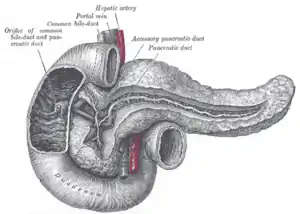

The pancreatic duct, or duct of Wirsung (also, the major pancreatic duct due to the existence of an accessory pancreatic duct), is a duct joining the pancreas to the common bile duct. This supplies it with pancreatic juice from the exocrine pancreas, which aids in digestion.

The pancreatic duct joins the common bile duct just prior to the ampulla of Vater, after which both ducts perforate the medial side of the second portion of the duodenum at the major duodenal papilla. There are many anatomical variants reported, but these are quite rare.[2]

Accessory pancreatic duct

Most people have just one pancreatic duct. However, some have an additional accessory pancreatic duct, also called the Duct of Santorini. An accessory pancreatic duct can be functional or non-functional.[3][4] It may open separately into the second part of the duodenum,[3][4] which is dorsal, and usually (in 70% of people) drains into the duodenum via the minor duodenal papilla. In the other 30% of people, it drains into the main pancreatic duct, which drains into the duodenum via the major duodenal papilla. The main pancreatic duct and the accessory duct both eventually—either directly or indirectly—connect to the second part ('D2', the vertical segment) of the duodenum.